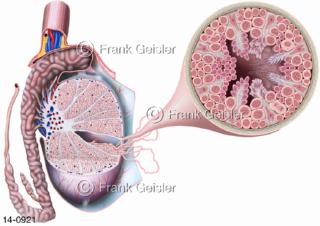

Bildergalerie Urogenitalsystem

Bilder zum Urogenitalsystem mit Urogenitalorgane, Urogenitaltrakt, zum Harn- und Geschlechtsapparat, Harnorgane und Geschlechtsorgane, Organe der Harnwege und der Fortpflanzung, Harnorgane und Geschlechtsorgane im männlichen und weiblichen Urogenitalsystem